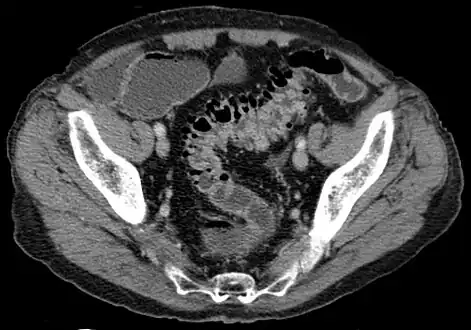

- Contrast CT is the investigation of choice in acute episodes of diverticulitis and where complications exist.

CT scan showing extensive diverticulosis of the sigmoid colon -

Diverticular disease -